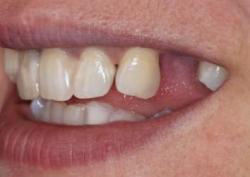

Примеры работ синус-лифтинга

Ежедневно мы восстанавливаем улыбку и уверенность в себе 5–7 пациентам.